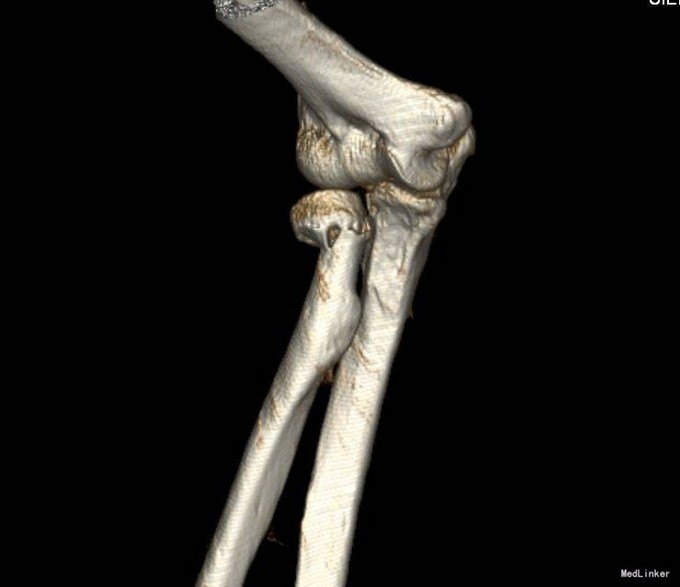

患者6小时前不慎摔倒,右手着地,当时即感右肘部剧烈疼痛,活动受限,被家人急送往奉天医院急诊,拍片检查示:右桡骨近端骨折,以“右桡骨骨折”收入院,现为进一步诊治,来我院就诊,以“右桡骨骨折”收入院,患者病来无头晕头痛,无恶心呕吐,无咳嗽咳痰,无发热寒战,饮食睡眠正常,二便正常,体重无明显减轻。

入院后完善检查,查无手术禁忌症后行右桡骨颈骨折切开复位内固定术,术后抗炎、接骨等对症治疗。术后第二天康复锻炼。术后2天一次换药,14天后出院。